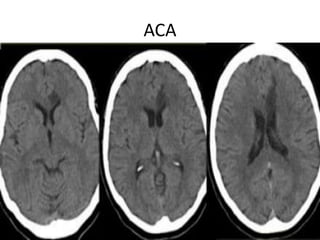

ACA